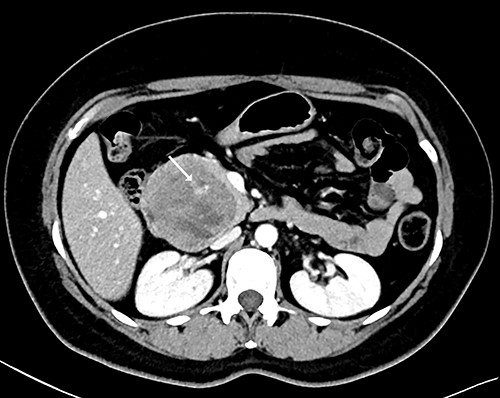

Two months later, she was scheduled for surgical treatment because of the SARS CoV2 pandemic peak. A new CT scan revealed a persistent 6 cm mass in the head of the pancreas, now containing air and communicating with the duodenal lumen (Fig. 3). A slight decrease in volume was also noted. The patient underwent a pancreatoduodenectomy with standard lymphadenectomy. The procedure took 240 min and involved 200 mL of blood loss. The patient was discharged 8 days postoperatively without complications. The histopathological examination showed a neoplasm of the head of the pancreas, with a solid and cyst appearance, and abundant haemorrhagic content. The neoplasm extended to the duodenum, causing fistulation to the lumen (Fig. 4). The immunohistochemical study showed expression of β-catenin, synaptophysin, vimentin and progesterone receptor (15%) and negativity for chromogranin, E-cadherin and CD117 (Fig. 5). The labelling index of Ki 67 was 2%, and the final diagnosis was a T3N0M0 SPN. The patient did not receive postoperative chemotherapy and has remained symptom-free with no detectable recurrence for 2 years of follow-up.

CT scan showing that tumour reduced to 6 cm, containing an air cavity (white arrow) and communicating with the duodenal lumen (arrowhead).